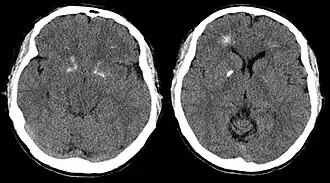

Le syndrome de délétion 22q11.2, appelé aussi communément syndrome de DiGeorge ou syndrome vélocardiofacial, est une pathologie en rapport avec une microdélétion de la région chromosomale dite de DiGeorge (DGCR), située sur le locus 22q11 du chromosome 22, et qui entraîne la perte du gène TBX1. Les enfants porteurs de cette mutation présentent des malformations cardiaques dans 75 % des cas de type conotroncale, et des anomalies de la partie supérieure de la bouche dans 70 % des cas. Ces anomalies correspondent sur le plan embryologique à une dysgénésie des 3e et 4e arcs pharyngés.

Des troubles biologiques existent, surtout une hypocalcémie en rapport avec une agénésie parathyroïdienne (PTH), et une hypoplasie thymique entraînant une immunodéficience congénitale touchant l'immunité à médiation cellulaire. 90 % des microdélétions 22q11 apparaissent de novo c'est-à-dire que les parents de ces enfants n'ont pas cette anomalie, alors que 10 % des enfants héritent cette délétion d'un de leurs parents.

Un retard mental existe chez un nombre significatif de ces enfants. Une schizophrénie est diagnostiquée chez un adulte sur cinq[3].

La cardiopathie congénitale la plus fréquente de ce syndrome est la tétralogie de Fallot, et nécessite un traitement chirurgical entre 3 et 6 mois de vie.